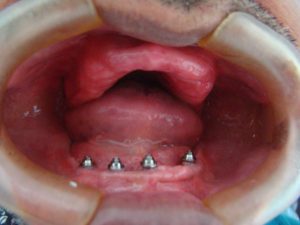

Veja os resultados de nossos pacientes

Implantes dentários são suportes ou estruturas de metal (normalmente de titânio) posicionadas cirurgicamente no osso maxilar abaixo da gengiva para substituir as raízes dentárias. Uma vez colocados, permitem ao dentista montar dentes substitutos sobre eles.